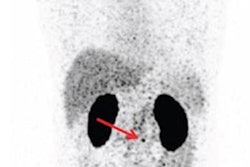

(a) Axial fused F-18 DCFPyL PET/CT through the prostate gland apex demonstrates significant avidity in location of pathologically proven 2-mm ISUP 5 left transition zone tumor (SUVmax 10.8) (arrow). (b, c) Axial DWI B value 2000 and corresponding ADC map demonstrate no abnormal restricted diffusion within the region of PET avidity (circle). (d) Axial T2 through prostatic apex demonstrates no suspicious signal characteristics at the site of the pathologically proven ISUP 5 transition zone tumor (circle). Image courtesy of Journal of Medical Imaging and Radiation Oncology.

(a) Axial fused F-18 DCFPyL PET/CT through the prostate gland apex demonstrates significant avidity in location of pathologically proven 2-mm ISUP 5 left transition zone tumor (SUVmax 10.8) (arrow). (b, c) Axial DWI B value 2000 and corresponding ADC map demonstrate no abnormal restricted diffusion within the region of PET avidity (circle). (d) Axial T2 through prostatic apex demonstrates no suspicious signal characteristics at the site of the pathologically proven ISUP 5 transition zone tumor (circle). Image courtesy of Journal of Medical Imaging and Radiation Oncology.The sensitivity of PSMA-PET in detecting csPCa was 96.7% and that of MRI was 93.4%, with no statistically significant difference between the two (p = 0.232). In addition, no additional clinically significant prostate cancer was identified on pathology that was not seen on imaging, according to the findings.